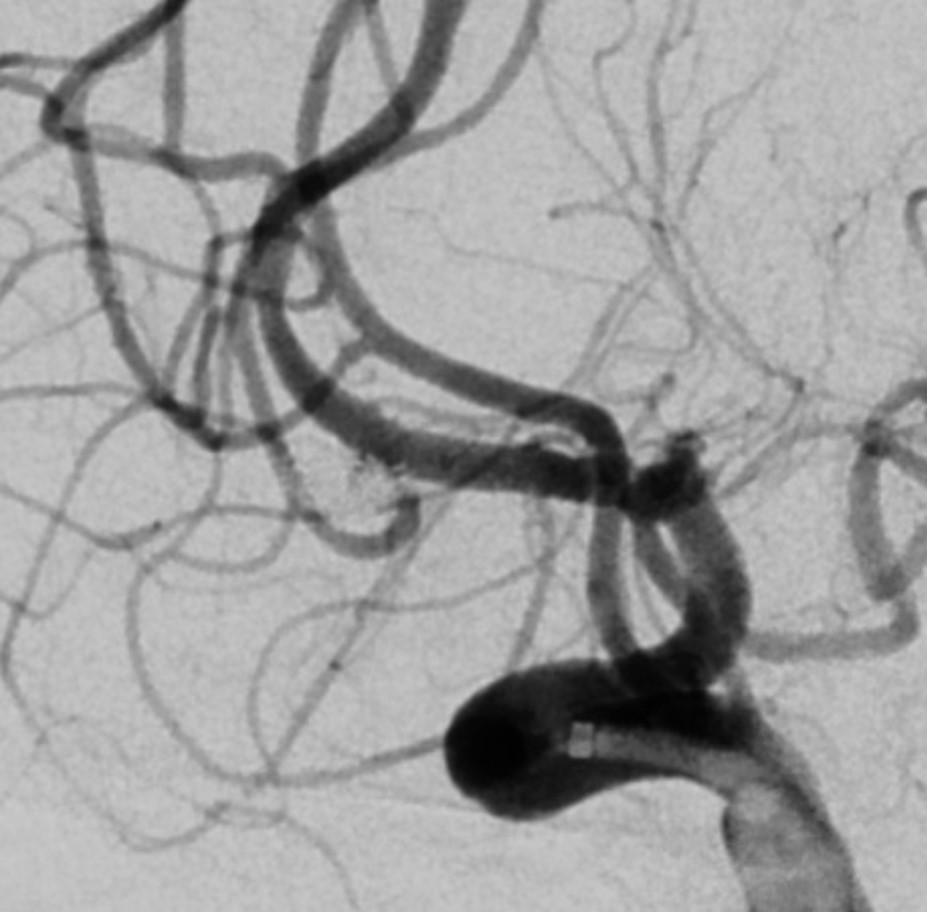

急诊行DSA发现:右侧大脑中动脉M1分叉部动脉瘤,瘤体大小:4.6*2.4mm,瘤颈宽约1.8mm,中动脉分叉下干成锐角自瘤体颈部发出。右侧大脑前动脉A1段动脉瘤,瘤体大小:3.0*2.5mm,瘤颈宽约1.5mm。

大脑中动脉瘤栓塞后即刻影像

栓塞6min及10min后再次造影,大脑中动脉下干前向血流仍然存在。

栓塞大脑中动脉瘤后6min造影

栓塞大脑中动脉瘤后10min造影

这是栓塞完大脑前动脉瘤之后的造影。在栓塞完大脑前动脉瘤的时候,我们手推造影剂发现中动脉下干前向血流消失,为防止中动脉下干急性闭塞,拟行支架植入术,但由于下干与中动脉主干呈锐角,超选失败。但在超选过程中发现微导管顶住瘤颈部弹簧圈后,下干前向血流恢复。

在撤掉微导管后,换角度进行造影,显示大脑中动脉下干闭塞。

造影显示大脑中动脉下干闭塞(栓塞大脑中动脉瘤后63min)

对比栓塞前及栓塞后进行的同角度造影,显示中动脉下干闭塞。后循环造影显示未见代偿。